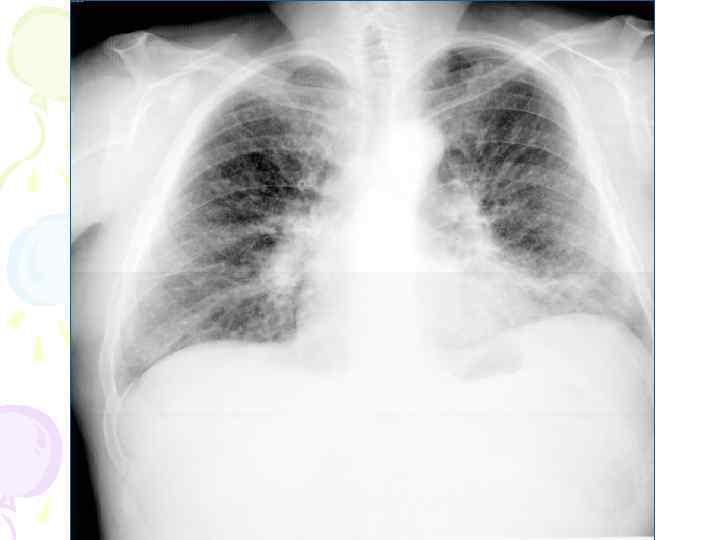

Рентгенологическая картина • множественные крупные / до 10 мм/ однотипные очаги преимущественно в верхних и средних отделах легких • Очаги округлой формы, малой и средней интенсивности, контуры нечеткие, часто расположены в виде цепочки вдоль продольных сосудов • Сливаясь, очаги образуют фокусы затемнения с участками просветления (распад) • При распаде в нескольких отдельных очагах формируются кольцевидные тени – штампованные каверны • При лимфогенной диссеминации очаговые тени с одной стороны, в средних и нижних отделах на фоне лимфангита, в корне кальцинаты